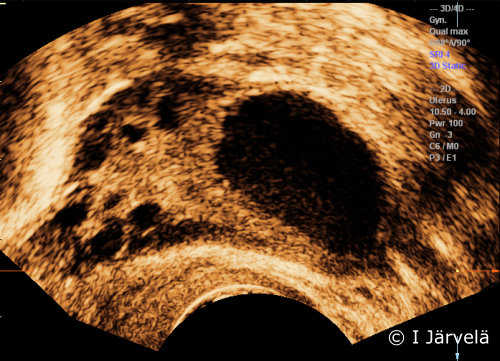

Kuva 1.

Keltarauhanen.

Keltarauhanen muodostuu dominantista follikkelista (ks. kuva

«Dominantti follikkeli (kaikukuva)»

1

).